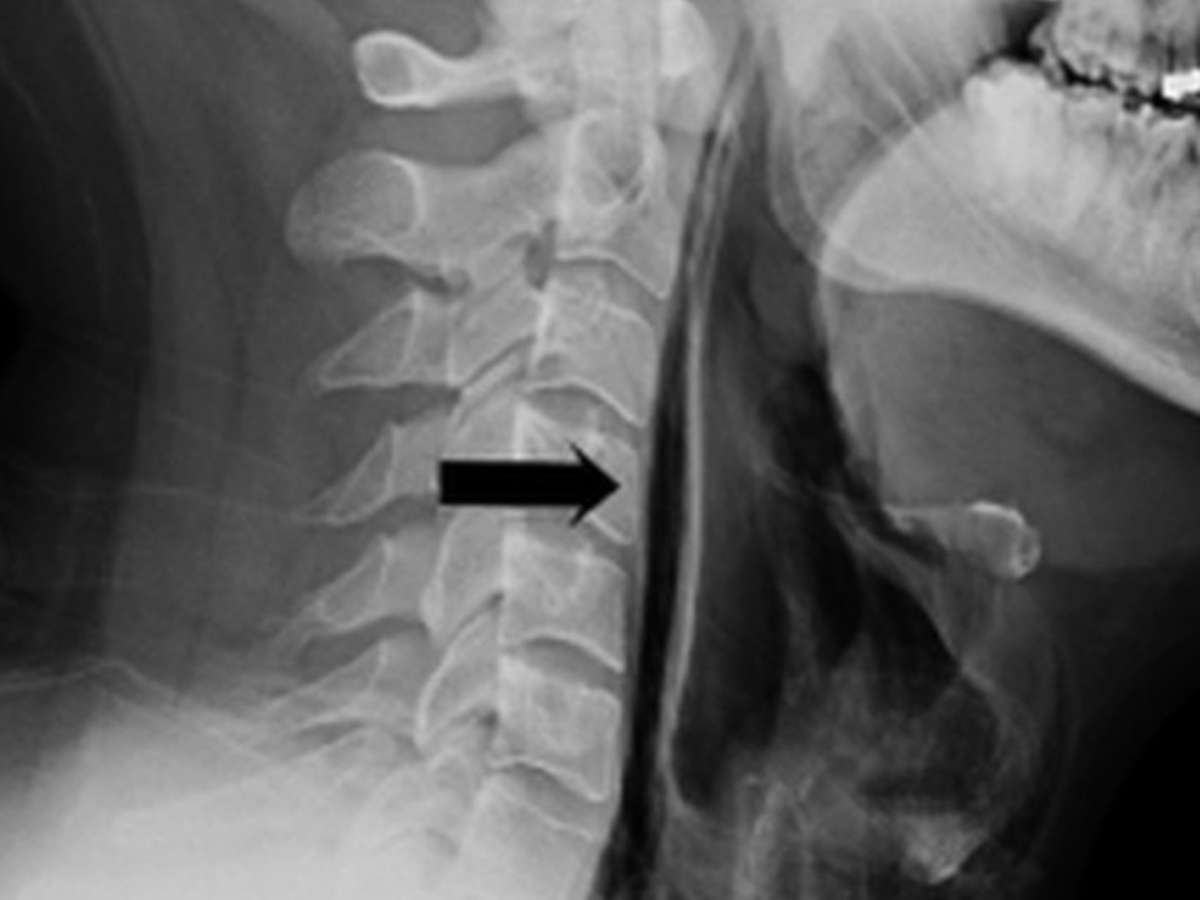

A flecha indica a fratura da garganta | Foto: BMJ

Como o espirro não tinha para onde escapar, a pressão rasgou o tecido mole da garganta. Um raio-X revelou que havia ar escapando da traqueia do paciente. Ele ficou internado por uma semana, recebendo alimentação via tubo, até se recuperar.